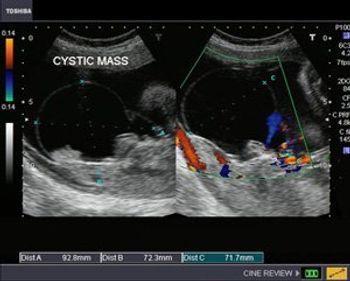

This case study shows a 26 week gestation with a cystic mass close to the sacrum.